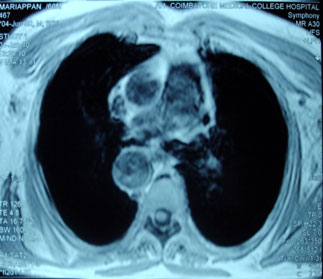

azygos vein (white arrow), Right sided aorta (white arrow head) MRI chest

shows fibrosis of mediastinum and right sided aortic arch